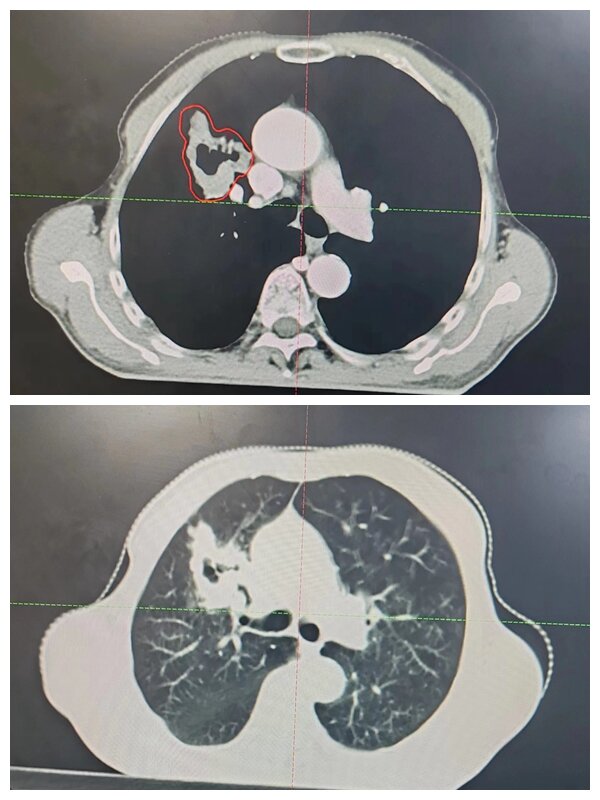

放療中

為盡可能保護好患者的心肺功能,使正常組織少受射線影響,放療科團隊嚴格控制脊髓、雙肺、心臟等器官受量,從CT定位到精確設(shè)計放療靶區(qū),從放療時間安排到每一次的擺位治療,從精心護理到營養(yǎng)支持干預(yù),每一個環(huán)節(jié)醫(yī)護人員都通力協(xié)作,盡最大努力為患者的健康保駕護航,治療期間患者耐受性良好,未出現(xiàn)嚴重不良反應(yīng)。經(jīng)過三周的治療,患者癥狀明顯緩解,病情得到有效控制。